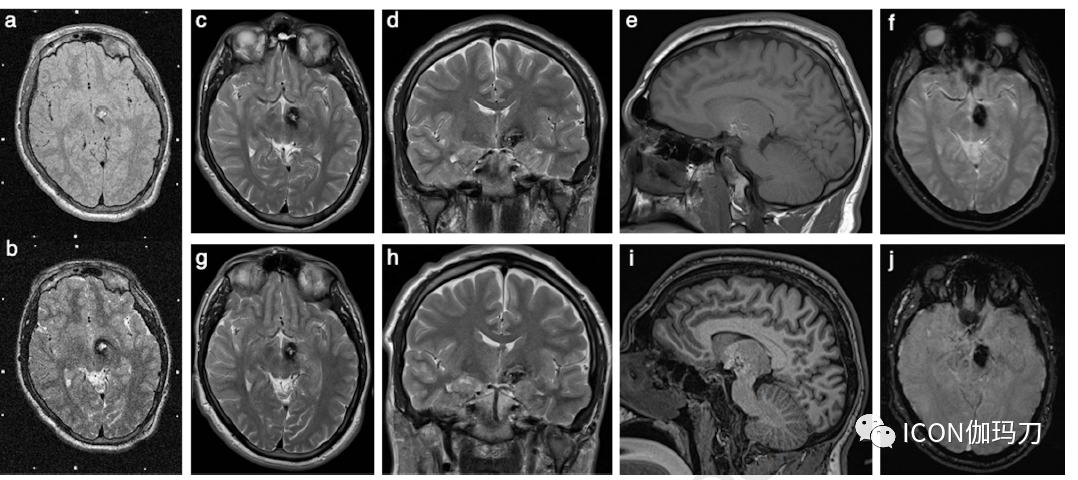

伽玛刀放射是放射外科中最受青睐的方法,因为它可以在保留周围组织的同时,为病变提供精确的辐射剂量。SRS相关并发症发生率的风险必须与反复出血的风险相平衡,后者的并发症发生率增加的风险要大得多。因此,对于“位置较深的”病灶,提倡更积极、更早的管理方法(a more active approach with earlier management for more ‘deep-seated’ lesions is advocated)。据报道,在SRS治疗后,孤立性CCM患者的再出血风险显著降低(图5),特别是对于有症状的脑干CCM患者,认为手术切除是高风险的。对于无法手术治疗和/或进袭性(aggressive)病灶,减少放疗剂量(边缘剂量为12-14 Gy)可能是一种合适的治疗选择,同时可以平衡弥补(counterbalancing)辐射诱发的损伤和SRS治疗后再出血的风险。

图5、一名有学习困难和自闭症谱系障碍病史的14岁男性患者的T2-WI轴位(a)质子密度和(b)SRS治疗前定位MRI。在(b)中左侧丘脑CCM的典型表现(中心高T1信号,外周含铁血黄素环低信号)比(a)中显现得更好。注意周围基准标记。随访MRI是在5年后(a)和“难以抬起头部”临床状态恶化(b)时进行的。选择(c)轴位T2-WI ,与SRS治疗前成像相比(a)和(b) ,(d)冠状T2-WI和(e)矢状T1-WI显示在左侧丘脑CCM含铁血黄素沉积增加。3年后获得了进一步的磁共振(c-f)和SRS治疗后8年22岁(a - b) 时他的行为恶化。与(f)相比,(g)轴位T2-WI、(h)冠状T2-WI、(i)矢状T1-WI和(j)轴位SWI在与(c-f)相同的水平上显示稳定的表现,(g)没有进一步的开花现象。注意(e)和(i)中存在气管内插管。